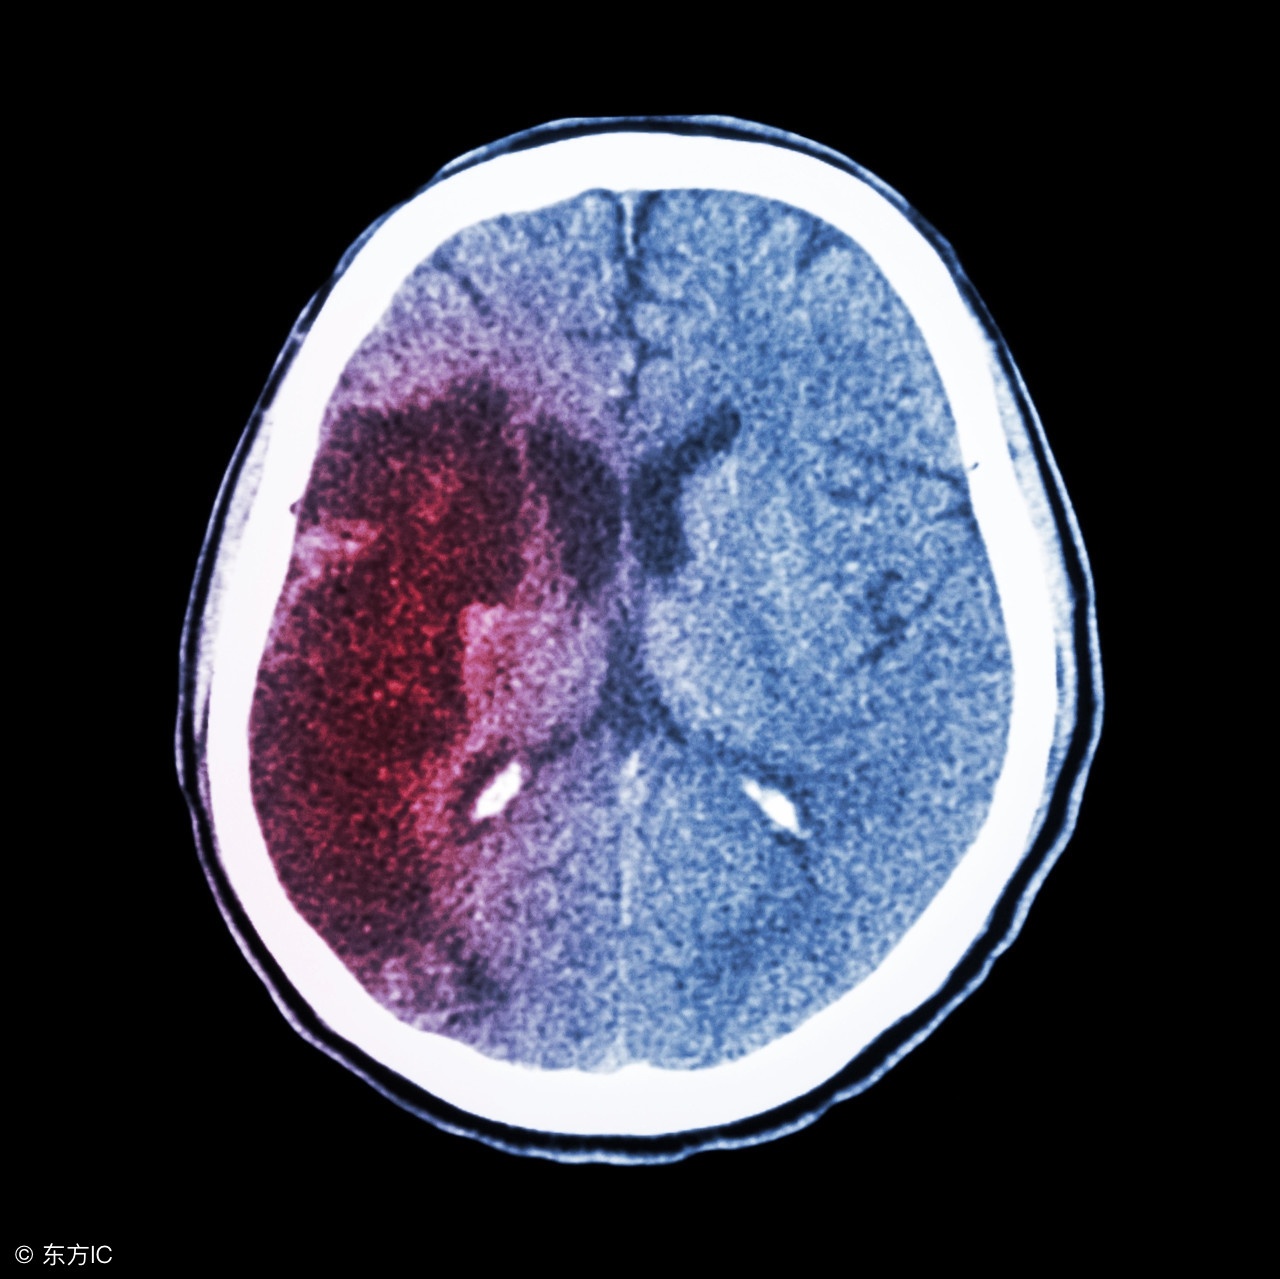

高血压脑出血手术后的饮食

注:文中图片来自网络,如有侵权请联系删除